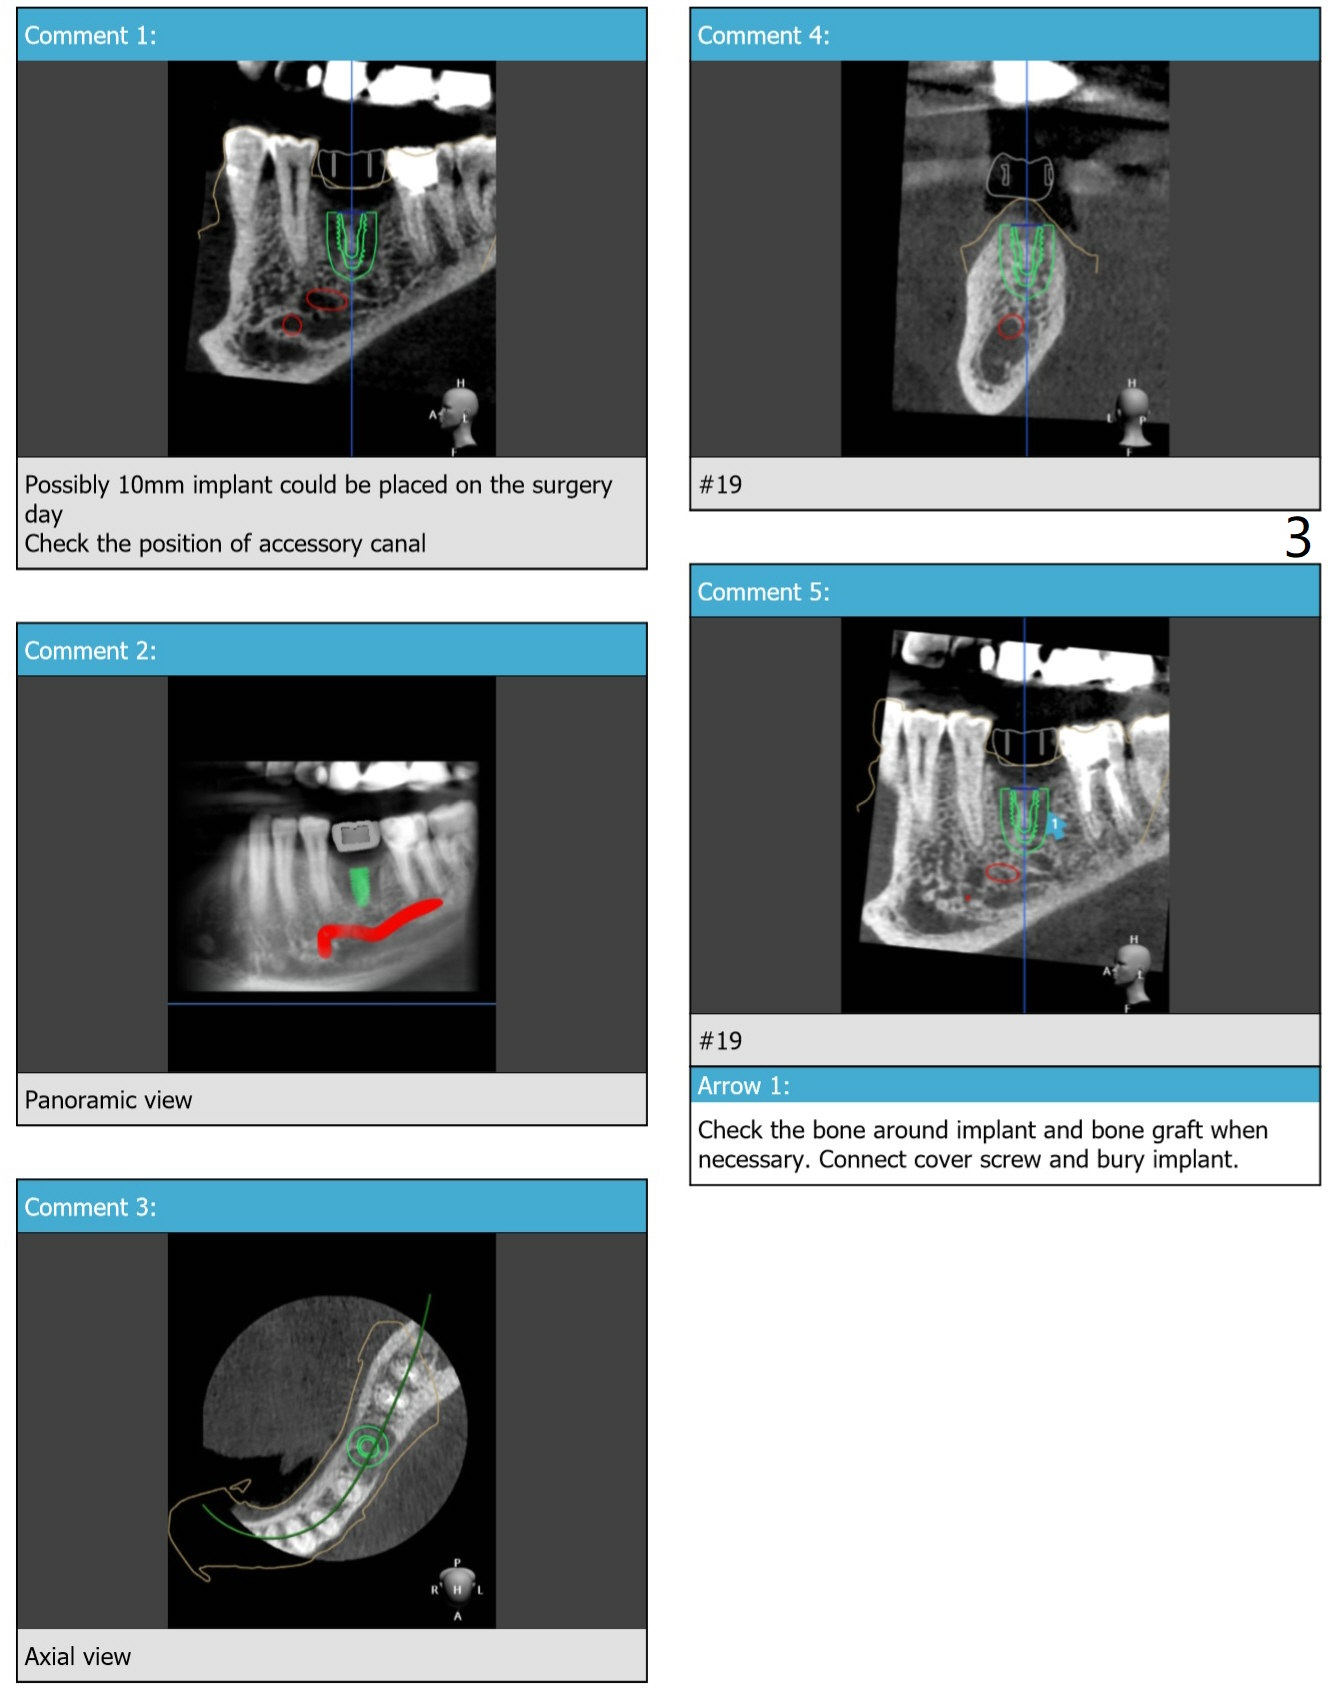

A narrow (extraction without bone graft) and short (accessory branch of nerve) implant is chosen at #19.